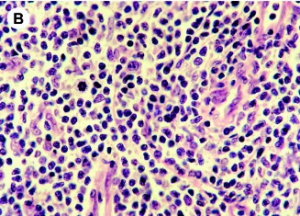

Les infections bactériennes sont d'ailleurs plus fréquentes chez les patients atteints de lymphome cutané dont la peau est plus fragile. Ces infections se multiplient avec le développement de la maladie. Le lymphome cutané à cellules T ou « T cutané » est caractérisée par une prolifération de cellules T malignes dans un environnement inflammatoire chronique. Avec la progression de la maladie, bactéries colonisent la barrière cutanée et la moitié des patients décède de l'infection plutôt qu'en raison de la malignité. Des données cliniques ont déjà montré le rôle direct des bactéries dans la progression de ce cancer. Cette étude décrypte les voies moléculaires de ce rôle bactérien.

In vitro, l'équipe montre à partir de prélèvements de tissus de peau affectée de patients atteints, et d'isolats bactériens qu'une toxine de Staphylococcus aureus (staphylococcal enterotoxin-A /SEA) stimule l'expression de 2 protéines, STAT3 et IL-17, dans les cellules T malignes ce qui favorise l'activation d'une voie oncogénique établie bien documentée dans le développement du cancer (carcinogenèse). En bref, via ses toxines, la bactérie « profite » aux cellules cancéreuses et favorise leur croissance. Dans le lymphome cutané, des cellules immunitaires spécifiques, les lymphocytes T CD4+ se transforment en cellules cancéreuses. L'étude montre que les toxines des bactéries permettent aux cellules cancéreuses d'envoyer des signaux qui perturbent le mécanisme de défense immunitaire, qui normalement devrait lutter contre les cellules cancéreuses. Les bactéries pourraient donc contribuer à rendre le lymphome de la peau soudainement plus agressif chez certains patients.